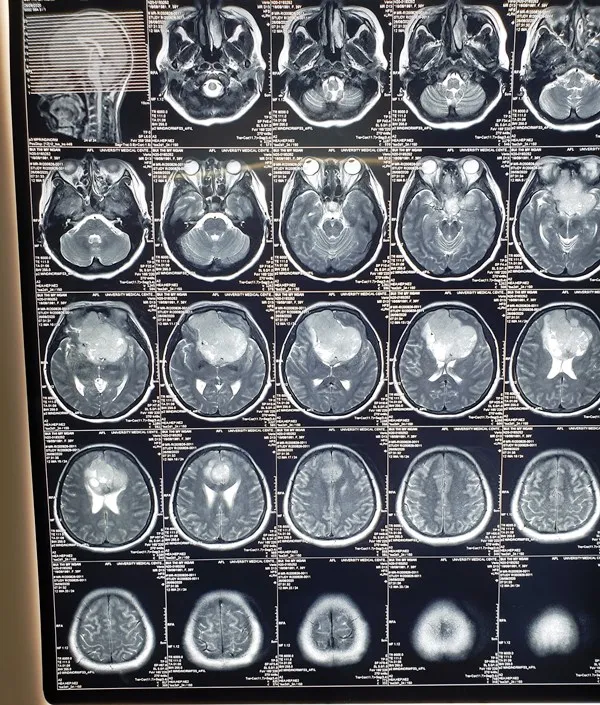

Ngay lập tức, bệnh nhân được các bác sĩ kiểm tra, kết quả chẩn đoán hình ảnh phát hiện bị màng não nền sọ và được chỉ định phẫu thuật. Tuy nhiên, việc phẫu thuật khối u phức tạp; ngoài ra, u không xâm lấn, nhưng dính vào các mạch máu lớn, trong quá trình phẫu thuật dễ gây tổn thương các mạch máu.

Để có thể phẫu thuật bóc tách lấy hết khối u, các bác sĩ phải phối hợp nhiều chuyên khoa. Đồng thời thực hiện chụp động mạch và nút mạch phần nuôi khối u làm giảm nguồn cung cấp máu cho khối u, giảm nguy cơ chảy máu khi phẫu thuật.

Do u quá lớn nên trong quá trình mổ phải cẩn thận để không tổn thương nhu mô não và các mạch máu lớn. Các bác sĩ của nhiều chuyên khoa đã phối hợp thực hiện lấy u vi phẫu, đây là phẫu thuật qua kính hiển vi, nên yêu cầu phẫu thuật viên thực hiện chính xác, tỉ mỉ, tiến hành đốt các mạch máu nuôi u, cầm máu…

Sau 10 giờ căng thẳng, các bác sĩ đã bóc tách thành công khối u và bảo tồn các cấu trúc quan trọng. Hiện bệnh tỉnh táo, không sốt, thị lực 2 mắt cải thiện tốt, không có cơn co giật cục bộ.